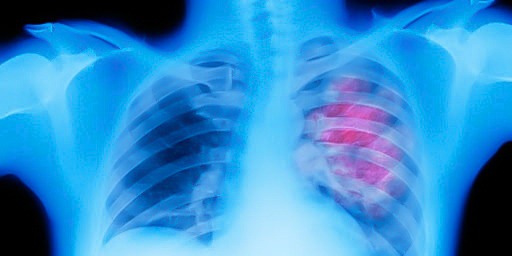

Mediastinal Tumors

Mediastinum is an anatomical region which is surrounded by thoracic cavity, thoracic entry on the top, diaphragm at the bottom, vertebral column at the posterior, sternum at the front and parietal pleura at the side. Mediastinum is divided into two as superior and inferior with a line extending from the anguli sterni to the fourth inter-vertebral…